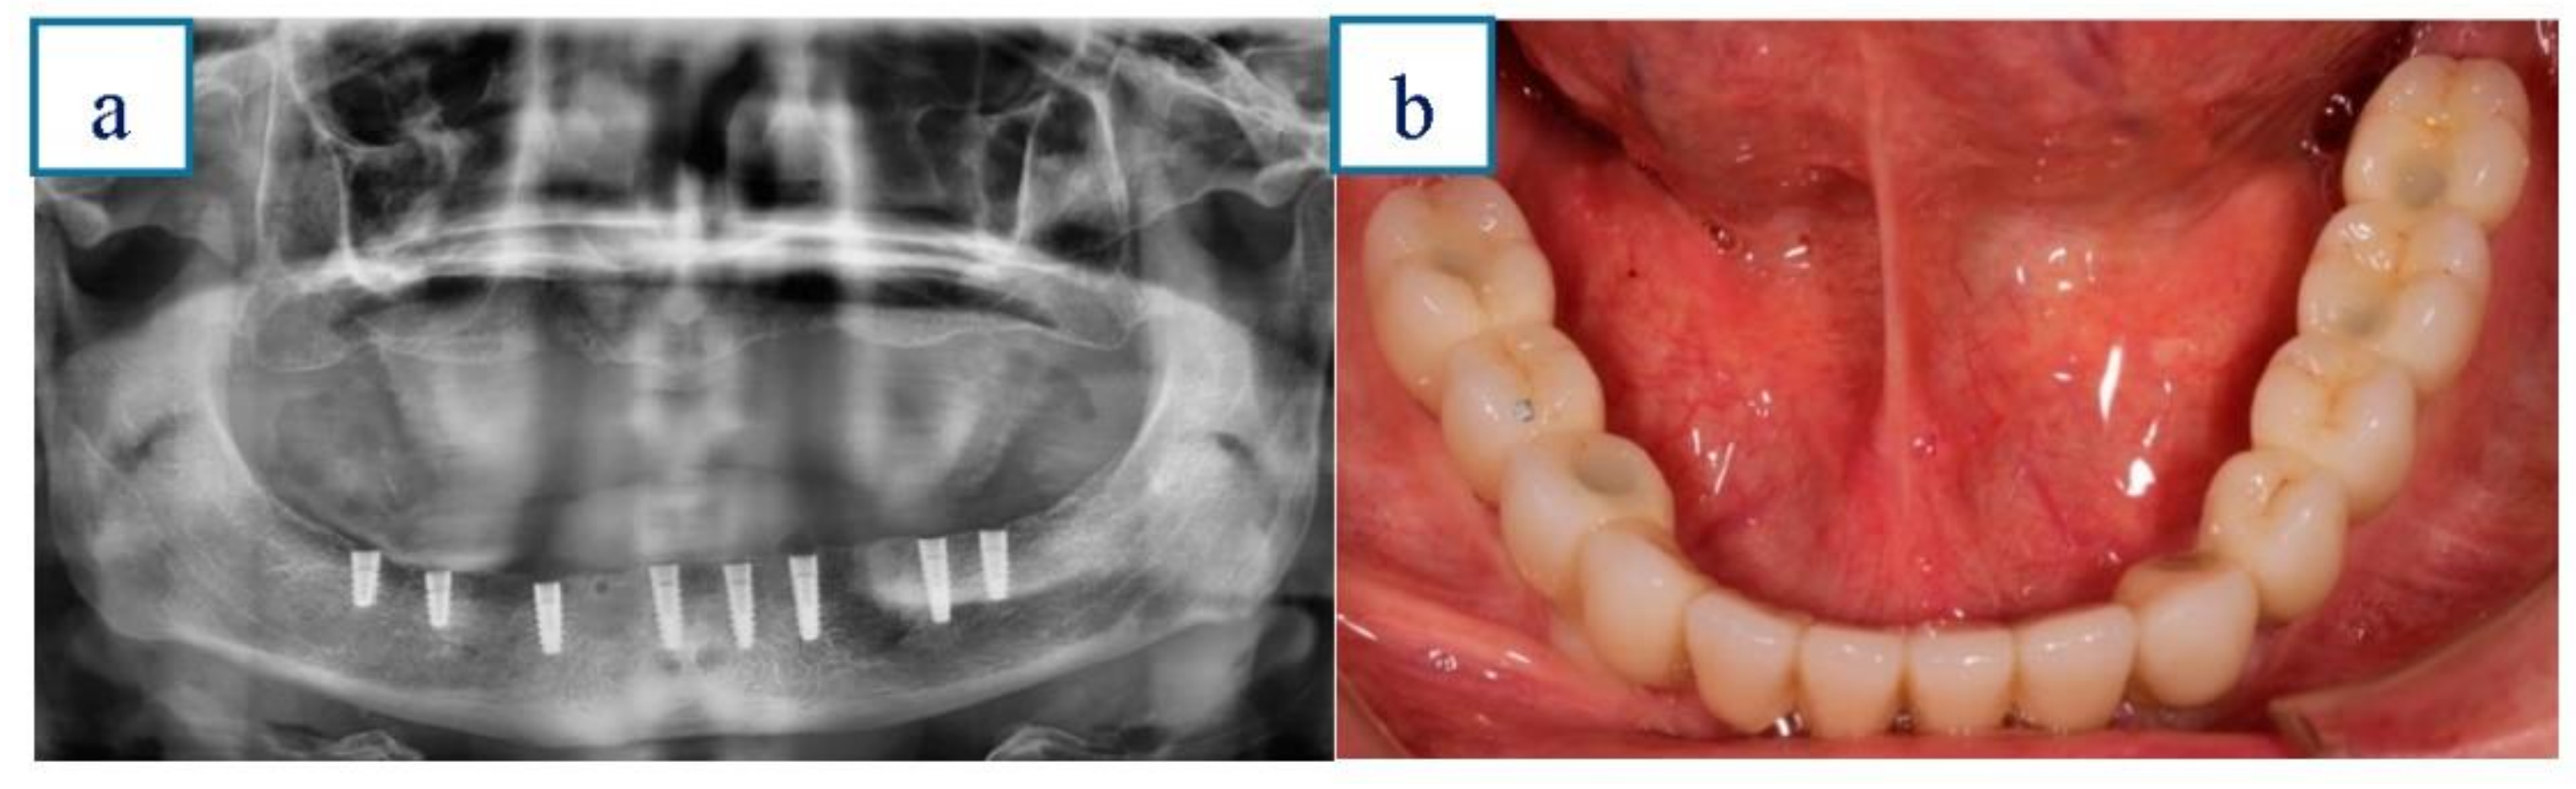

Immediate Loading of Implants Placed by Guided Surgery in Geriatric Edentulous Mandible Patients

Velasco-Ortega, E.; Jiménez-Guerra, A.; Ortiz-Garcia, I.; Moreno-Muñoz, J.; Núñez-Márquez, E.; Cabanillas-Balsera, D.; López-López, J.; Monsalve-Guil, L. Immediate Loading of Implants Placed by Guided Surgery in Geriatric Edentulous Mandible Patients. Int. J. Environ. Res. Public Health 2021, 18, 4125. https://doi.org/10.3390/ijerph18084125